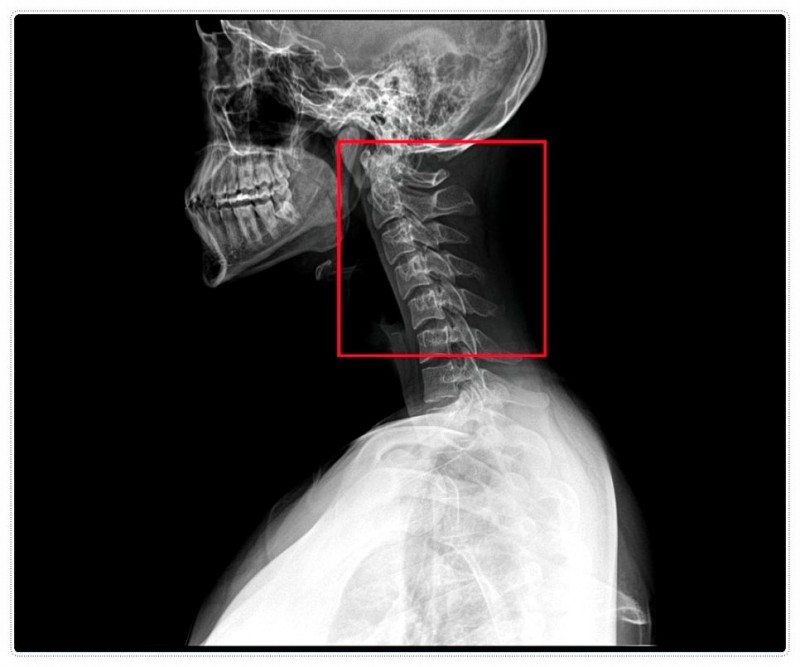

Q. 목뼈 1, 2번이 뭐길래 그렇게 중요한가요?

목을 지탱하는 가장 위쪽 뼈인 경추 1·2번은 턱관절과 바로 연결돼 있습니다.

그래서 턱이 한쪽으로 틀어지면 그 영향이 목뼈로 전달되고,

목뼈는 다시 어깨와 척추에 연쇄적으로 부담을 주게 되죠.

이 과정에서 신경과 혈관이 눌리면

통증, 두통, 손 저림 같은 증상이 나타날 수 있습니다.